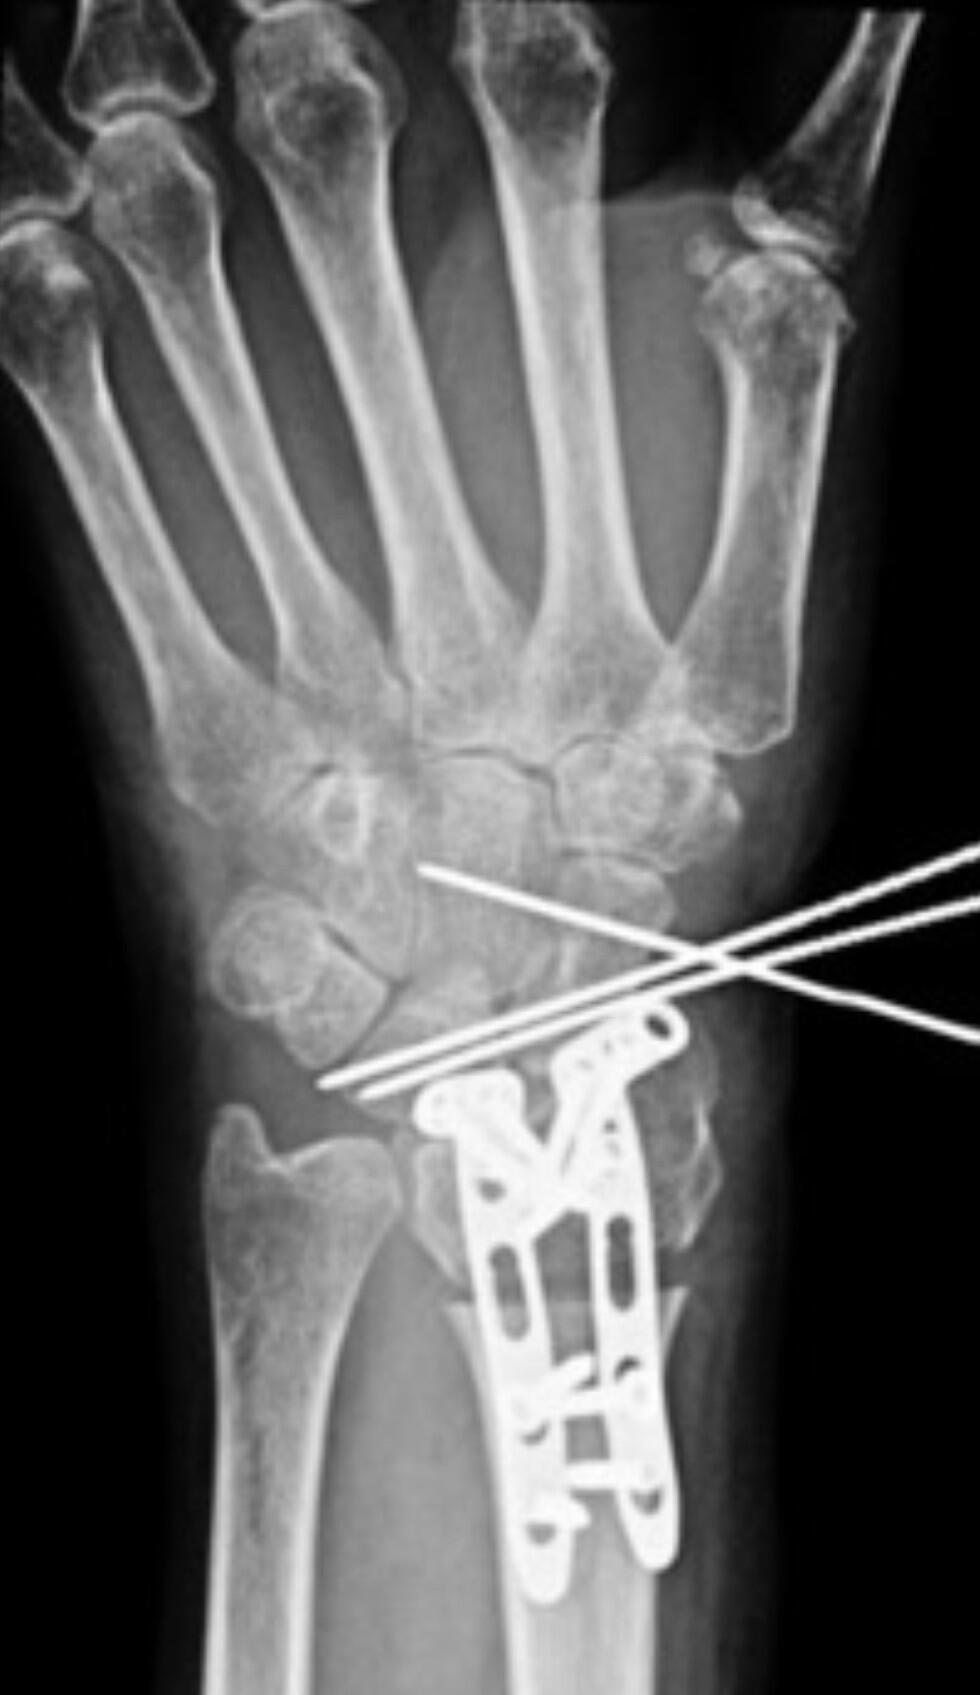

Рентгенограмма кисти 57-летней женщины, у которой не заживал перелом запястья из-за привычки набирать текстовые сообщения. Снимок предоставлен д-ром Лурьe